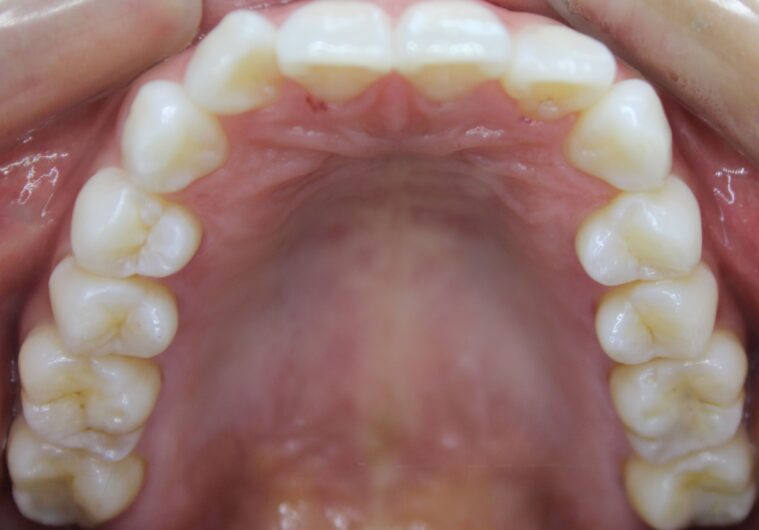

下の画像は、先日アマルガム充填をグラディア充填に換えた方の画像です。

こちらは審美というよりも、ご自身の身体の為にお薦めしている治療です。

グラディア充填によって、身体にもよくて、見た目も綺麗なら言うことないですね。

ちなみにグラディアとは、硬質レジンで保険のレジンよりも着色しにくく

綺麗に修復出来るので、お勧めです。